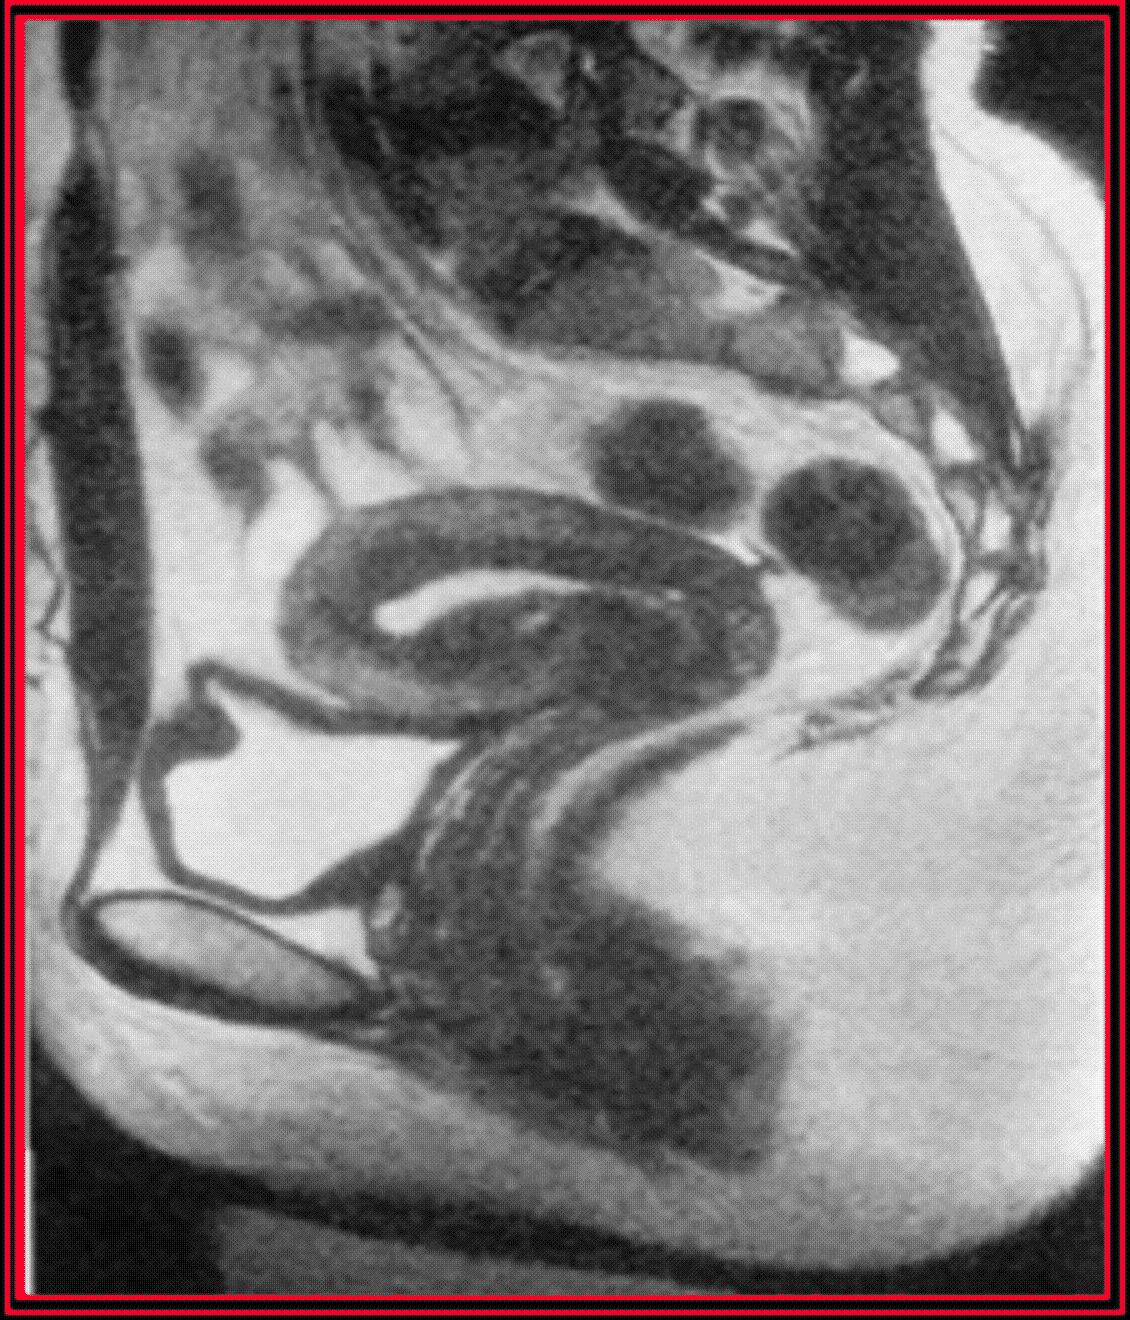

Il existe deux techniques de préhension du sol, soit l'appareillage traditionnel à l'aide d'une canule de Riazzi-Palmer, soit la ventouse cervicale à embout de Bommelaer, qui est moins douloureuse. Après la saisie du col, il faut enlever le spéculum, pour permettre une bonne vision du col et de l'endocol. Le début de l'examen commence par la prise d'un cliché sans préparation. L'opérateur doit exercer une forte traction sur le col pour redresser l'utérus, on injecte lentement 0,5 ml de liquide de contraste et le premier cliché est pris, c'est le cliché de remplissage précoce qui permet de voir la cavité corporéale. Ensuite, après injection lente de 2 à 3 ml, on réalise le cliché de remplissage complet qui renseigne sur la cavité, l'isthme et le fuseau endocervical, le contrôle téléradioscopique permet de vérifier le début du remplissage tubaire. La troisième étape est le cliché de profil, la patiente est placée en décubitus latéral, jambes repliées l'une sur l'autre, il faut lâcher momentanément la traction sur le col pour permettre à l'utérus de retrouver sa position naturelle. Ce cliché de profil renseigne sur la position de l'utérus, sur l'état de l'isthme et du col et sur la position des trompes. On reprend ensuite la traction sur le col et on injecte 1 à 2 ml pour réaliser le cliché d'évacuation sur lequel outre la cavité, les trompes seront analysées. La dernière étape est le cliché tardif, 15 à 20 minutes après, qui permet d'apprécier la perméabilité tubaire, la sténoseDéfinitionModification anatomique qui se traduit par un rétrécissement d'une structure (canal, vaisseau). ou la perméabilité des pavillons, d'éventuelles adhérences péritonéales, la forme le volume des fossettes ovariennes.

De face en réplétion complète et après traction sur le col, de manière à placer la cavité utérine dans le prolongement du col, elle à la forme d'un triangle isocèle à base supérieure. Sa capacité oscille entre 3 et 10 ml environ. La longueur du fond et des bords est en moyenne de 3 à 4 cm. Le fond et les bords utérins sont rectilignes. Dans certains cas, il est possible au cours du cliché de remplissage de mettre en évidence, dans la région sus-isthmique, des images linéaires parallèles aux bords qui correspondent à des plis muqueux. De profil, la cavité utérine est fusiformeDéfinitionQui a la forme d'un fuseau, c'est-à-dire qui a ses deux extrémités se terminant en pointe.. Lorsque l'utérus est antéversé, elle forme avec le canal cervical un angle de 120° environ. Lorsque l'utérus est en position intermédiaire, le fond utérin se projette en direction de l'ombilic. En cas de rétroversion utérine, il se projette en regard du promontoire (rétroversion du premier degré), de la première pièce sacrée (deuxième degré) ou de l'articulation sacro-iliaque (troisième degré).

Les trompes

Elles comportent 4 segments :

- La portion intra-murale traverse le myomètre et mesure 1 à 2 cm environ de longueur sur 0,4 de largeur. Son origine est souvent marquée par un renflement triangulaire,

- L'isthme mesure 3 à 4 cm de longueur. Il est fin, souvent sinueux et parfois mal visible, du fait des superpositions d'images. Son calibre réduit s'explique par l'épaisseur de sa paroi qui empêche son expansion,

- L'ampoule mesure 6 à 8 cm de longueur sur 0,5 à 1 cm de largeur. Son calibre s'élargit insensiblement et sa limite radiographique avec l'isthme est très nette,

- Le pavillon et l'ostium tubaire sont difficilement visibles lorsque le produit hydrosoluble diffuse largement le long des franges du pavillon. En cas de rétrécissement lié à un phimosis tubaireDéfinitionRétrécissement d'une ou des deux trompes utérines, aboutissant à une obturation tubaire partielle ou totale. Un phimosis tubaire est souvent consécutif à une salpingite (infection d'une ou des 2 trompes) non traitée. Les franges du pavillon de la trompe s'agglutinent, se resserrent et se collent les unes aux autres, sans que la patiente ressente généralement aucun symptôme. Le phimosis est ainsi le plus souvent découvert à l'occasion d'un bilan de stérilité (hystérographie et/ou cœlioscopie). Le traitement, chirurgical, cherche à rétablir la perméabilité de la trompe et la fertilité de la femme : décollement des parois de la trompe et éversion des franges du pavillon. Cette intervention est généralement pratiquée par cœliochirurgie (introduction d'une optique et des instruments chirurgicaux par de petites incisions abdominales)., cette région devient particulièrement nette.

La position de la trompe est très variable et varie suivant la parité et l'âge. L'existence de plis muqueux, parallèles à l'axe de l'ampoule traduit un aspect normal.

Après diffusion le long des franges du pavillon, le produit cerne assez fréquemment la surface externe des ovaires, réalisant l'image des fossettes ovariennesDéfinitionFossette ovarienne : Zone située latéralement dans le pelvis, limitée en avant par l'artère ombilicale, en arrière par l'uretère et l'artère iliaque interne et en haut par la veine iliaque externe.. On peut ainsi indirectement apprécier le volume des ovaires (normalement 3,5 cm de long sur 2 cm de large).

Le passage péritonéal

Affirmé parfois dès les premiers clichés, il s'apprécie en fait sur le cliché tardif. Il se traduit par un aspect marécageux occupant le petit bassinDéfinitionPetit bassin ou pelvis minor : Cadre osseux, sensiblement hémisphérique, de la forme et de la taille d'un petit bol, situé à la base du bassin, sous la cavité abdominale. et qui est obtenu par le brassage du produit provoqué par la mobilité des anses intestinales.